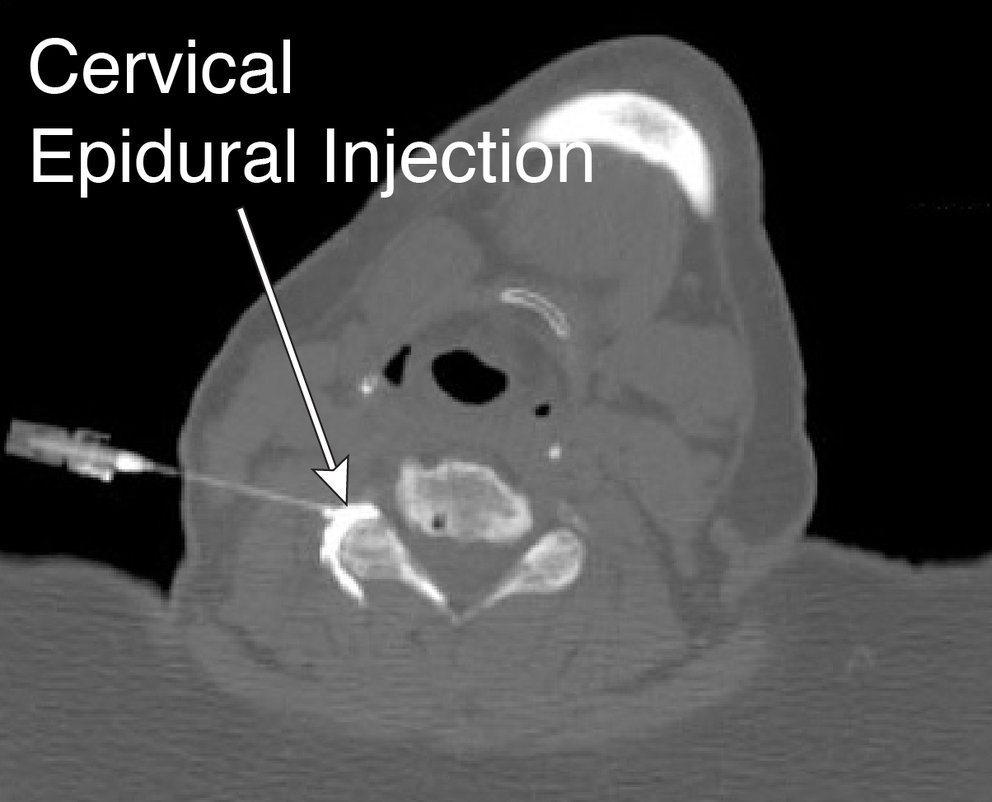

Cervical Epidural Steroid Injection New South Medical Why No Heat After Epidural Steroid Injection however, there are two golden rules as to what you should do after an epidural steroid; This includes steam rooms, saunas, and hot packs, but your. Heat can increase inflammation at the injection site and interfere with the effectiveness of the medication. If you do have side effects, they may include: Steroid flush, or flushing of the face and. Why No Heat After Epidural Steroid Injection.

Cervical Epidural Steroid Injection Minnesota Institute For Pain Why No Heat After Epidural Steroid Injection Heat can increase inflammation at the injection site and interfere with the effectiveness of the medication. an epidural steroid injection generally causes no problems. avoid heat to the injection site for 3 days. First you need to rest and take things easy. why no heat after epidural steroid injection? however, there are two golden rules as. Why No Heat After Epidural Steroid Injection.